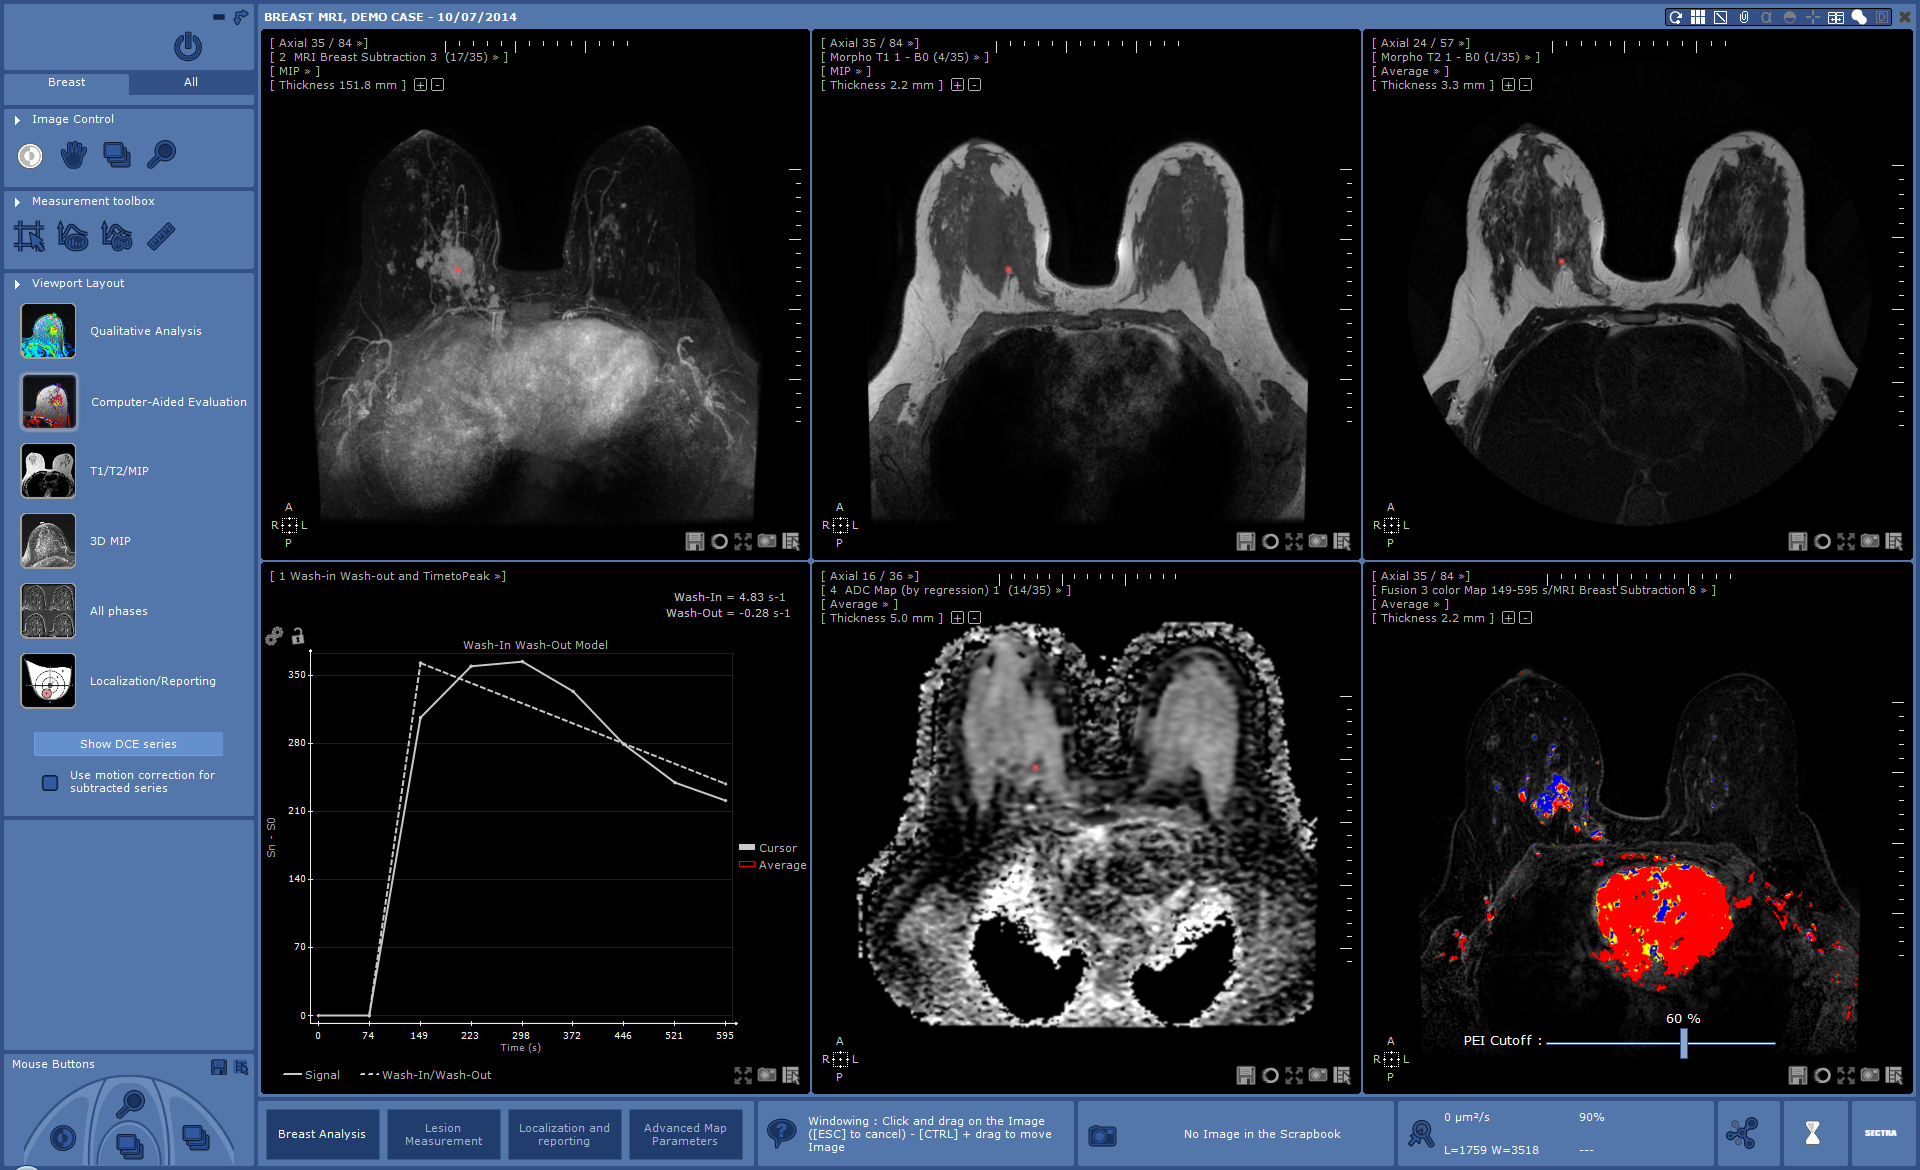

A key in achieving an efficient breast imaging reading workflow is to give radiologists the opportunity to read in a focused and undisturbed environment. Radiologists should not have to move between different workstations to read images from different modalities. For example, if your mammography clinic is considering including breast tomosynthesis or breast ultrasound in the screening workflow, you need to have a PACS which supports a multi-modality workflow.

Another important factor to consider if you are about to invest in a PACS, is that mammography radiologists often use specialized applications such as CAD. Looking further down the road, new applications will emerge to improve the reading workflow. Accordingly, it is key that the PACS can integrate with third-party applications. Having to launch another application just to do a CAD analysis is a real efficiency killer. Make sure that your PACS vendor understands integration and has a PACS strategy to integrate it all into a single workspot.

“Sectra already provides the most comprehensive breast imaging solution in the market, enabling our customers to have a streamlined high volume workflow in one single application, and will continue to do so. One example of Sectra’s commitment to provide the most efficient breast imaging solution in the market is our extensive integration program with third-party applications from more than 60 different vendors. This allows the radiologist to maintain a single workspace even when adopting new technologies and avoid having to move to modality-specific workstations for diagnosis,” says Anders Granlund.